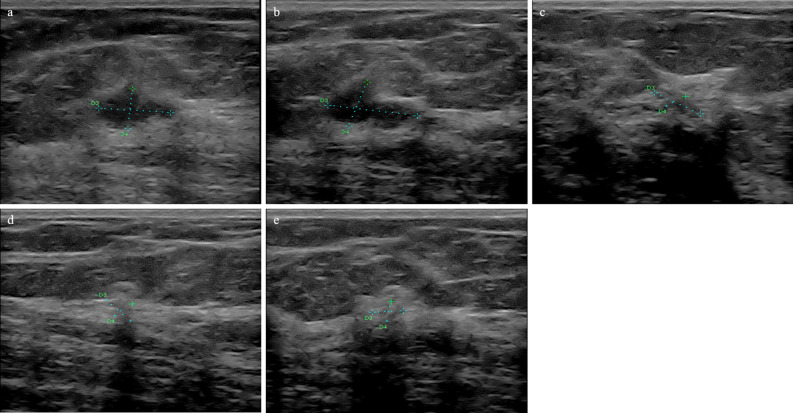

Examples of B-mode images for the case N-RT (RMC = 100%) and RT (RMC = 0) are shown in Figs. 2 and 3, respectively.

Figure 2.

Ultrasound results from a 56-year-old patient with breast cancer (NST Grade 3, TNBC, Ki 67–30%). In B-mode examination (a) before treatment, the tumour was hypoechoic. After the first (b), second (c), third (d), and fourth (e) course of the NAC, the echogenicity increased (histopathological verification: RT, RMC = 0).